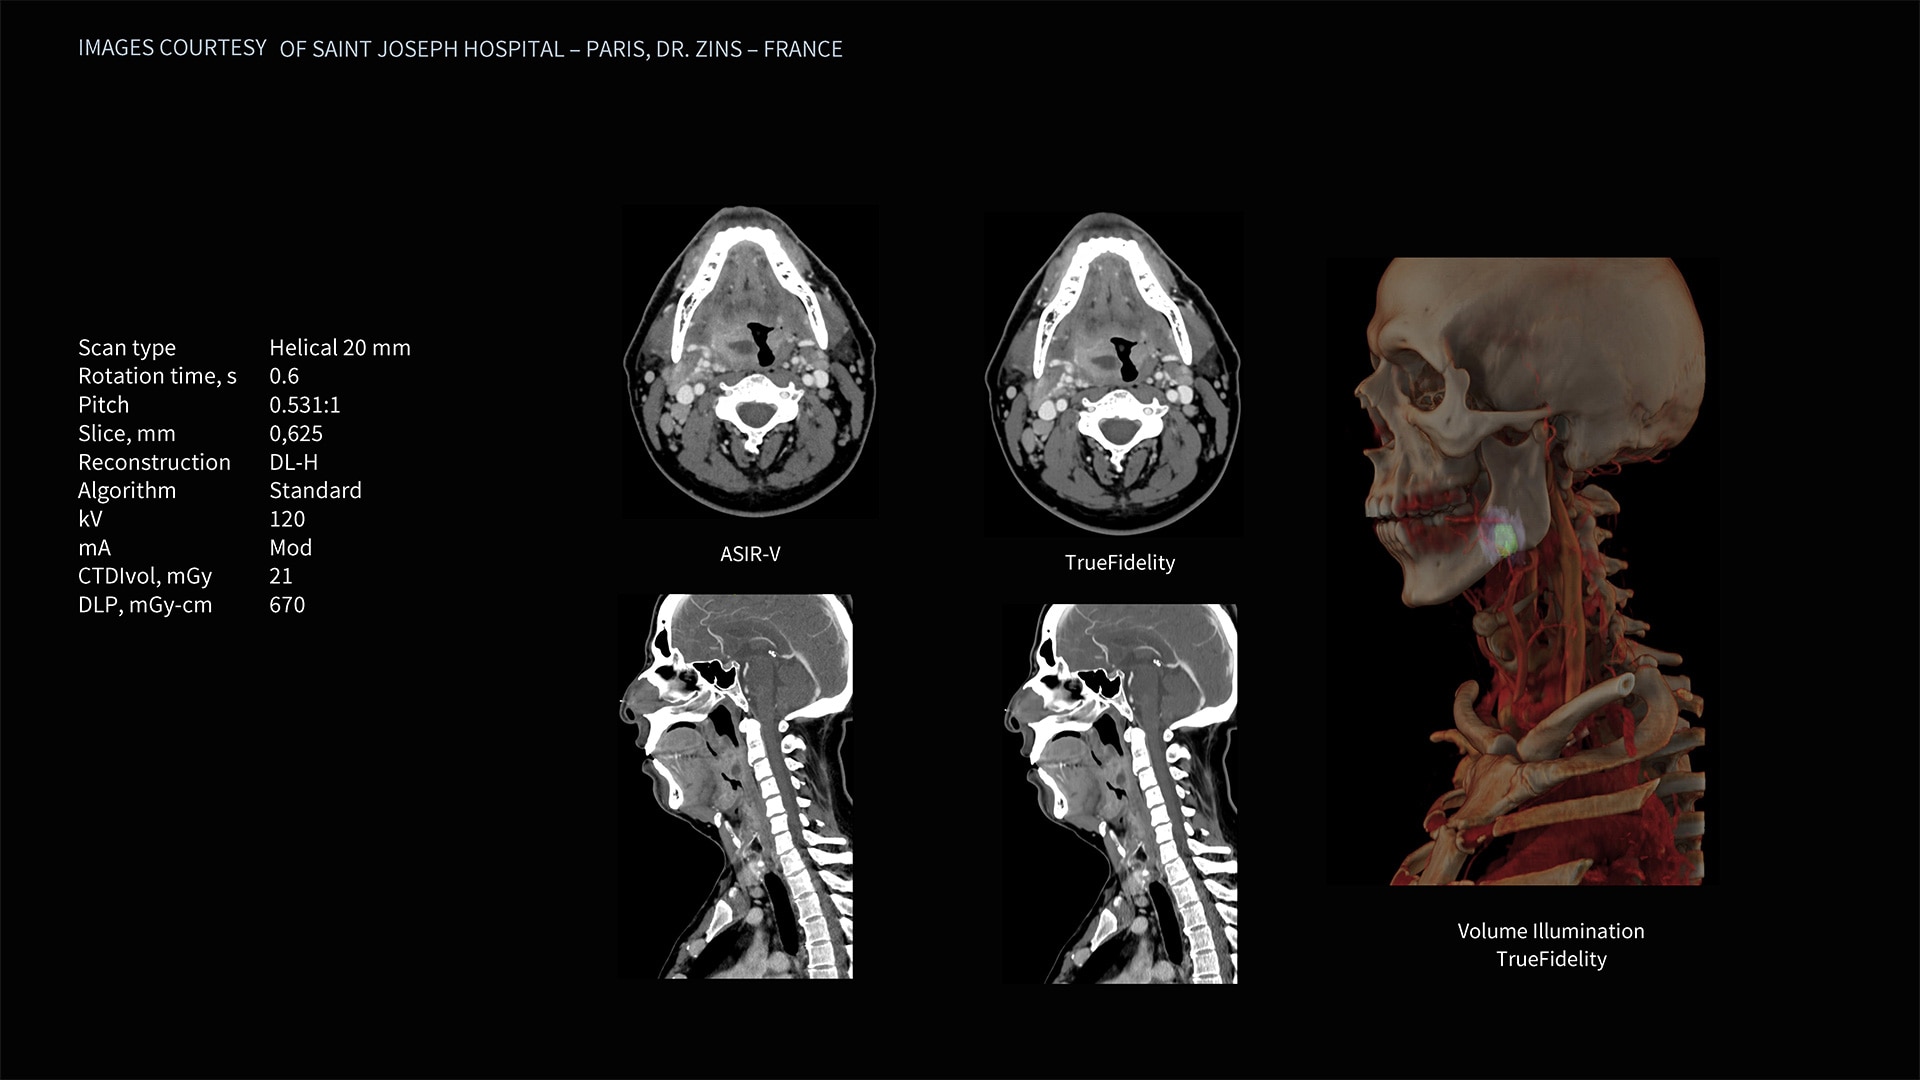

Deep learning image reconstruction, higher special resolution at 0.23 mm

Address individual clinical needs, moving seamlessly from one scan mode to the next. Image with a stunning 0.23 mm spatial resolution, then switch to rapid kV switching for full 50 cm FOV spectral imaging of the entire body. Choose up to six times reduction in motion artifact using SnapShot Freeze 2¹ for coronary artery CTA and reduce all-round dose with next-generation iterative reconstruction.